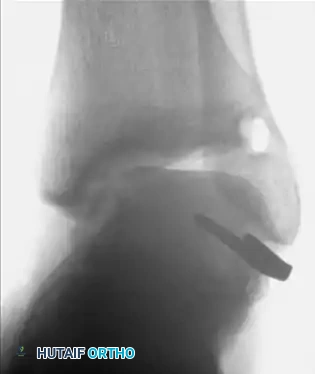

Associated Surgical & Radiographic Imaging